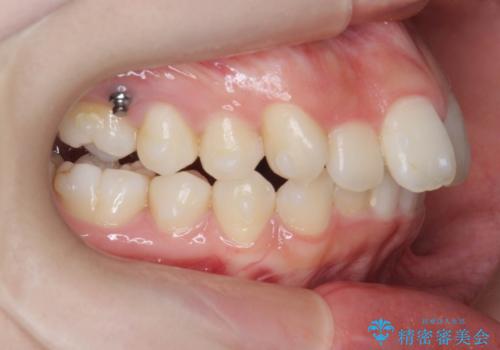

途中顎位が変わり、マイクロインプラントを併用した上顎臼歯の遠心移動が必要となったため治療が長期化しました。